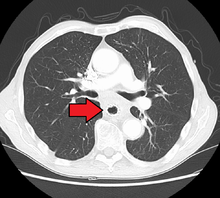

Additional testing is needed to assess how much the cancer has spread (see #Staging, below). Computed tomography (CT) of the chest, abdomen and pelvis can evaluate whether the cancer has spread to adjacent tissues or distant organs (especially liver and lymph nodes). The sensitivity of a CT scan is limited by its ability to detect masses (e.g. enlarged lymph nodes or involved organs) generally larger than 1 cm. Positron emission tomography is also used to estimate the extent of the disease and is regarded as more precise than CT alone. Esophageal endoscopic ultrasound can provide staging information regarding the level of tumor invasion, and possible spread to regional lymph nodes.

Contrast CT scan showing an esophageal tumor (axial view)

Contrast CT scan showing an esophageal tumor (coronal view)